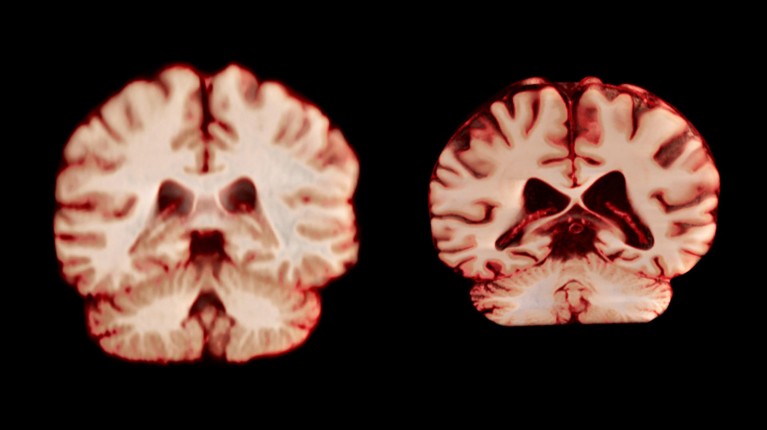

Здрав мозак (лево) и мозак који су погођени Алзхеимеровом болешћу. КРЕДИТ: Анатомски путопис / СПЛ

Најновија студија је обухватала више од 12,500 магнетних резонанца (МРИ) скенирања мозга са 4.726 људи – најмање два скенирања по особи, узела је у просеку три године, која није имала Алзхеимерова болест или било какве когнитивне оштећења и учесници контроле у 14 већих података. Истраживачи су упоредили како се мозга појединца током времена промијениле, гледајући факторе, укључујући дебљину сиве материје и величину подручја која су повезана са Алзхеимеровом болешћу, попут хипокампуса, која је од суштинског значаја.

Све у свему, мушкарци су доживели веће смањење волумена у више региона мозга него жене. На пример, последња кортекса, која је одговорна за обраду сензација додира, боли и температуре, као и сопствени положај тела и кретања, смањена је за 2,0% годишње код мушкараца и за 1,2% годишње код жена.

Ако су ове промене имале улогу у развоју Алзхеимерове болести, студија би показала да ће жене доживети већи пад у областима повезаним са болешћу, попут хипокампуса и пре пре давања, који су укључени у меморију, каже Ами Бродтманн, клиничарски истраживач у Монасх Универзитету, каже Ами Бродтманн, Ами Бродтманн, а Ами Бродтманн у Монасх Универзитету у Монасх-у.